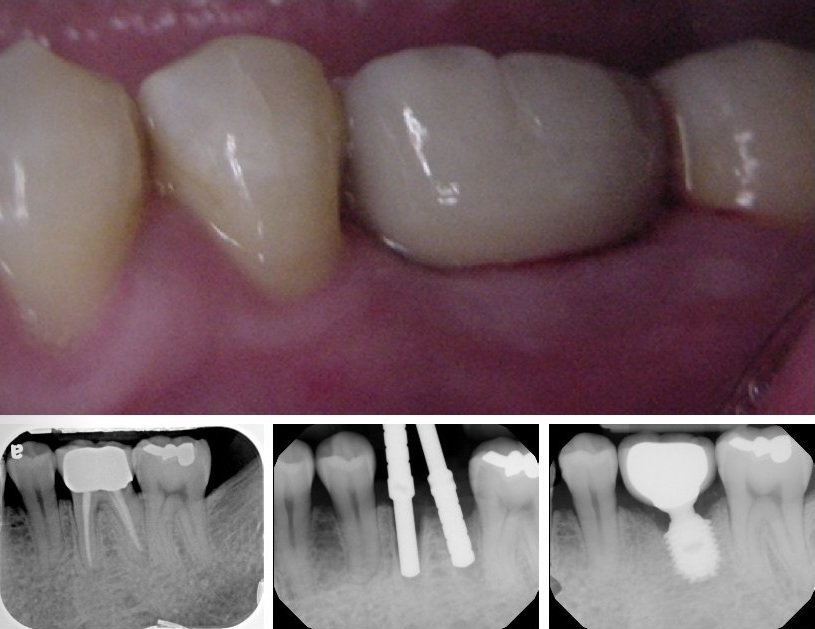

Short Implants and Sinus Lift

Implant Supported Bridges